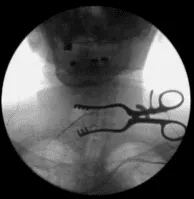

Se utilizaron disecciones romas y separadores portátiles Cloward para acercarse a la columna cervical anterior. Se usaban Kittners para barrer la fascia prevertebral. Se colocó una aguja espinal en el interespacio C5-C6. La unidad C-arm fue colocada de forma estéril, llevada al campo y utilizada para confirmar el nivel.

Se utilizó el monopolo Bovie para exponer la columna cervical anterior de C4 a C6, socavando los músculos del largo del cóleo bilateral. Se instaló un sistema de separador autoretenedor TrimLine. Se colocaron clavos de cáscaro de 12 mm en los cuerpos vertebrales anteriores C4, C5 y C6. Se aplicó primero una retracción suave en C5-6.